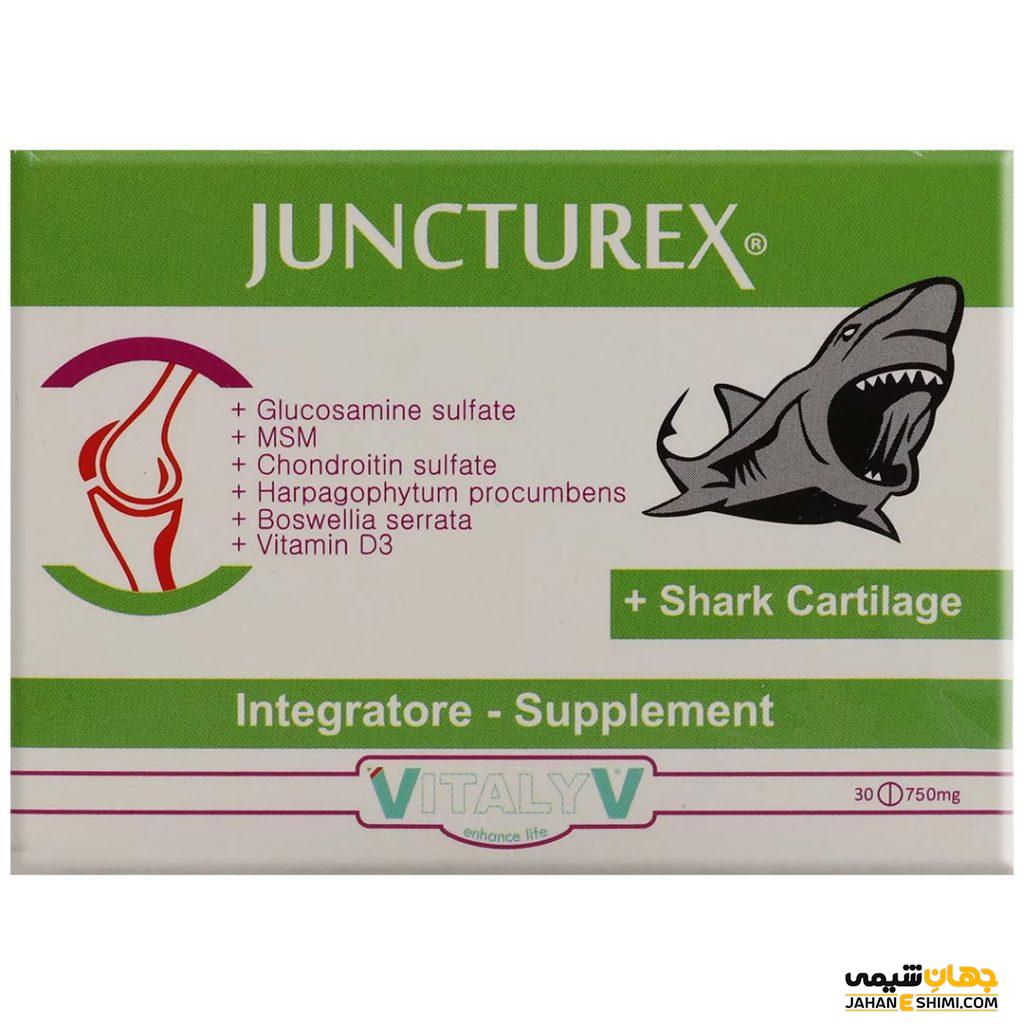

قرص جانکتورکس ویتالیو چیست؟ موارد و نحوه مصرف و عوارض آن

قرص جانکتورکس ویتالیو ترکیبی از گلوکزامین، ام اس ام، کندرویتین سولفات، شارک کارتیلیج و ویتامینD3، عصاره گیاهان هارپاگوفیتوم و بوسولیا سراتا است و سبب تقویت عملکرد مفاصل و سبب نگهداری از استخوان ها میشود. در نشریه جهان شیمی فیزیک از انواع مکملها مقالاتی منتشر شده است. در این مطلب اطلاعاتی در مورد قرص جانکتورکس ویتالیو در اختیارتان قرار میدهیم.

قرص جانکتورکس ویتالیو چیست

قرص جانکتورکس ویتالیو ترکیبی از گلوکزامین، ام اس ام، کندرویتین سولفات، شارک کارتیلیج و ویتامین D3 به همراه عصاره هارپاگوفیتوم و بوسولیا سراتا است. سبب تقویت عملکرد مفاصل و جذب کلسیم و فسفر می شود

موارد مصرف قرص جانکتورکس ویتالیو

تقویت عملکرد مفاصل و نگهداری استخوانها

نحوه مصرف قرص جانکتورکس ویتالیو

دو قرص در روز به همراه آب مصرف گردد.

احتیاط در مصرف قرص جانکتورکس ویتالیو

قرص جانکتورکس ویتالیو مکمل غذایی است و برای تشخیص، پیشگیری و درمان نیست.

ویژگی قرص جانکتورکس ویتالیو

تقویت عملکرد مفاصل

کاهش التهاب و درد مفاصل

پیشگیری از فرسودگی مفاصل

مصرف مکملها و قرص جانکتورکس ویتالیو

مصرف قرص جانکتورکس ویتالیو در بهبود مشکلات مفاصل و آسیبهای استخوانی موثر است.

شرایط نگهداری از قرص جانکتورکس ویتالیو

قرص جانکتورکس ویتالیو، دور از دید اطفال و نور و در جای خشک و خنک قرار دهید.